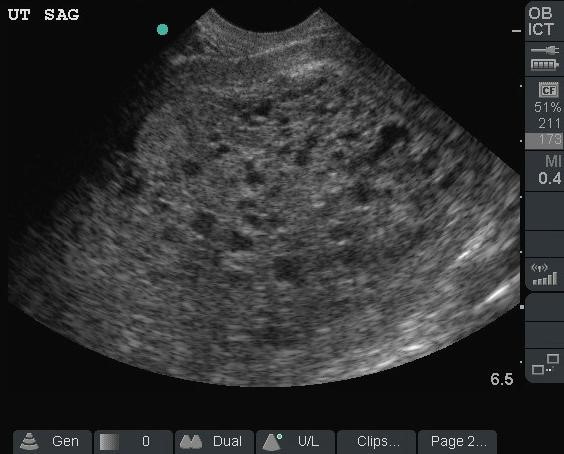

Sonographic Technique – Transabdominal

- Use of a 3.5-5 MHz curvilinear probe or phased array probe.

- Start just above the pubic symphysis in the transverse (probe indicator to the patient’s right).

- In the transverse plane use the bladder as an acoustic window to identify the uterus. Fan all the way through by angling the beam towards then head and fan towards the feet. The endometrial stripe should be a hyperechoic line in the middle of the uterus.

- Rotate the probe towards the patient’s head to and fan left to right in the sagittal plane (Illustrations 5 & 6, Video 2)